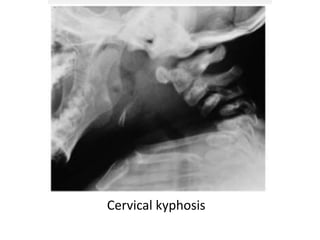

Cervical kyphosis